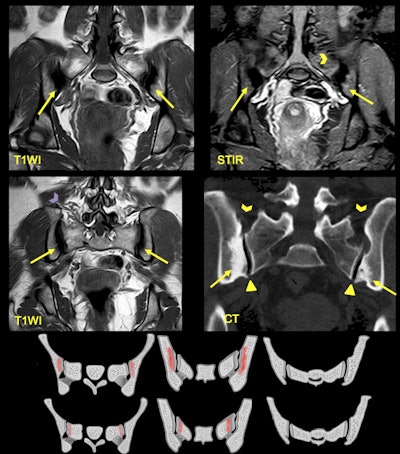

A 25-year-old woman presented with lower back pain and a history of two pregnancies. MRI shows areas of sclerosis (arrows) with low signal intensity on T1WI that arise along the iliac surface with bilateral and symmetric affection. CT shows triangular shape of the iliac bone sclerosis and lack of joint erosions. Note there is no joint space narrowing (triangle) in respect of the ligamentous compartment (arrowheads).